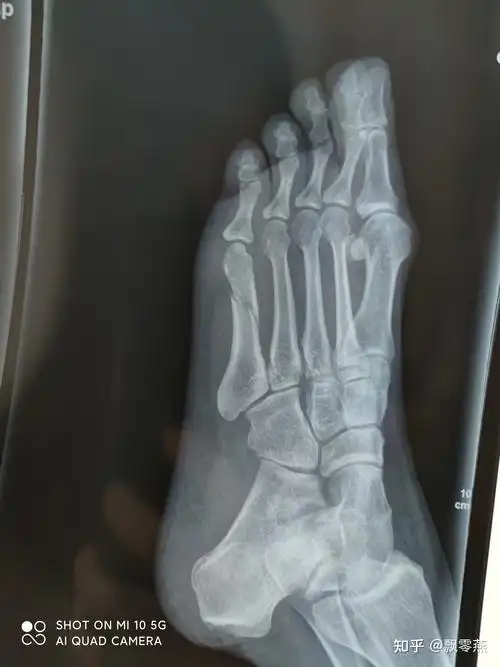

60天不放心还去拍了片子,骨折线已经模糊,但是错位的地方还是没有连接